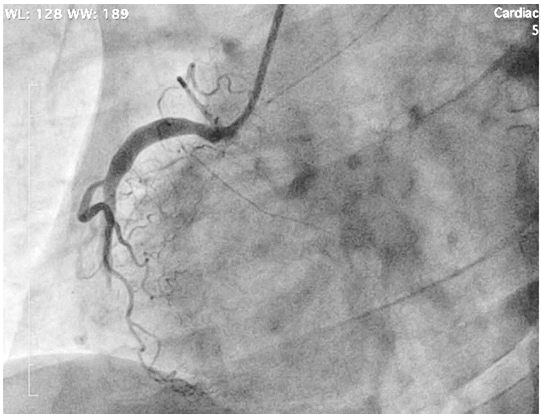

A coronariografia na projeção oblíqua anterior esquerda acima é compatível com a seguinte emergência cardiovascular: